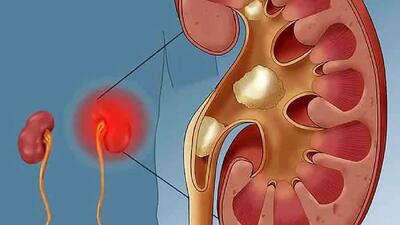

نارسایی کلیه

رابطه مصرف مسکن در بیماران میگرنی و آسیب به کلیه

یک جراح کلیه و پروستات با اشاره به پیشگیری و درمان بیماریهای کلیوی توضیحاتی ارائه کرد.

عدم کنترل قند خون موجب نارسایی کلیه

فوق تخصص کلیه دانشگاه علوم پزشکی بابل عدم کنترل قند خون را موجب نارسایی کلیه دانست.

راه های محافظت از سلامت کلیه ها

رکنا: سلامت کلیه ها بسیار مهم است.

اهمیت تستهای سالانه عملکرد کلیوی از ۴۰ سالگی به بعد

نارسایی مزمن کلیه یک بیماری خاموش است که فرد مبتلا ممکن است سالها از آن بیاطلاع باشد؛ علل ایجاد کننده این بیماری، اغلب به بیماریهای دیابت و فشار خون بالا بازمیگردد.